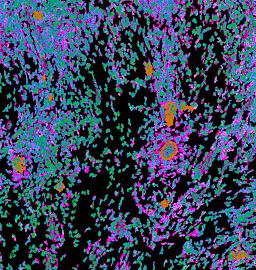

Pancreatic ductal adenocarcinoma is a lethal disease with limited treatment options and poor survival. We studied 83 spatial samples from 31 patients (11 treatment-naïve and 20 treated) using single-cell/nucleus RNA sequencing, bulk-proteogenomics, spatial transcriptomics and cellular imaging. Subpopulations of tumor cells exhibited signatures of proliferation, KRAS signaling, cell stress and epithelial-to-mesenchymal transition. Mapping mutations and copy number events distinguished tumor populations from normal and transitional cells, including acinar-to-ductal metaplasia and pancreatic intraepithelial neoplasia. Pathology-assisted deconvolution of spatial transcriptomic data identified tumor and transitional subpopulations with distinct histological features. We showed coordinated expression of TIGIT in exhausted and regulatory T cells and Nectin in tumor cells. Chemo-resistant samples contain a threefold enrichment of inflammatory cancer-associated fibroblasts that upregulate metallothioneins. Our study reveals a deeper understanding of the intricate substructure of pancreatic ductal adenocarcinoma tumors that could help improve therapy for patients with this disease.